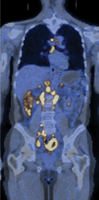

Tumor Growth and Detection

The progression of a tumor from a single mutated cell to a clinically detectable mass involves multiple cell divisions and population doublings.

Growth Curve: Tumors become detectable by imaging or palpation only after reaching a critical size, often after many population doublings.